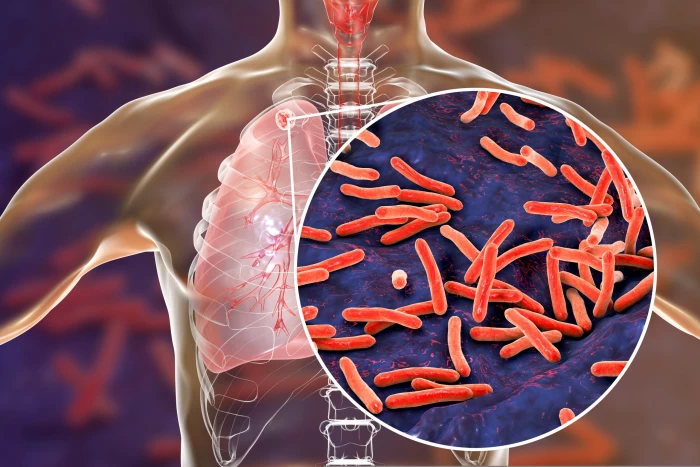

Medicul atrage atenția că tuberculoza face parte din categoria bolilor care transmit foarte ușor pe cale respiratorie sau prin secrețiile nazale rezultate din tusea pacientului infectat. Pentru a preveni răspândirea infecției, specialiștii recomandă tuturor care prezintă simptome precum tuse, strănut sau secreții nazale să poarte mască. Mai ales în apropierea minorilor și a copiilor. De asemenea este recomandat consultarea unui medic de specialitate care să investigheze simptomele.

„Pentru prevenirea infecţiei este necesar ca orice persoană care are simptome respiratorii ca tuse, secreţii nazale, strănut să poarte o mască de protecţie atunci când este în prezenţa altor persoane, mai ales în prezenţa copiilor, să meargă la medicul pneumolog şi să se investigheze imediat ce aceste simptome apar”, a adăugat medicul Radu Crişan Dabija.